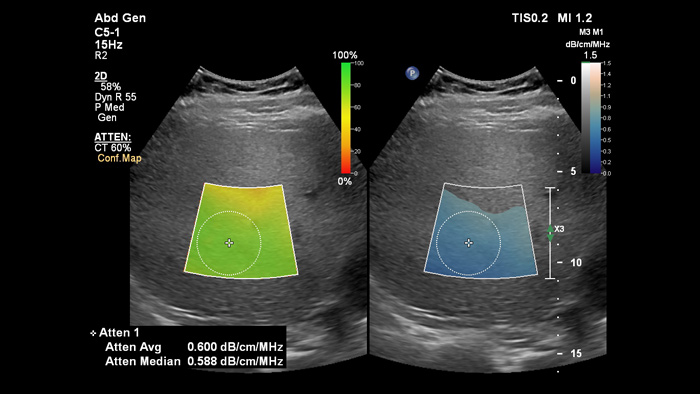

Attenuation Imaging can measure the amount of fat present in the liver by calculating the attenuation coefficient of sound abnsorbed by the liver parenchyma. This method provides quantitative attenuation parameters that can help assist physicians in the management of patients with hepatic steatosis.

Attenuation imaging